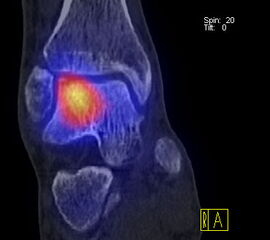

Die Kombination von SPECT und CT in einem Untersuchungsgang bringt wie bereits oben erwähnt eine erhöhte Ortsauflösung und artefaktfreie Darstellung von Knochenstoffwechselveränderungen der SPECT bei gleichzeitig excellent guter anatomischer Darstellung/Zuordnung durch die CT 3. Auf die Vorteile der CT gegenüber dem konventionellen Röntgen muss nicht mehr besonders eingegangen werden. Besonders eignet sich die „SPECT-CT“ zur Diagnostik von Fußerkrankungen (Biersack HJ et al. 2012).

Aufgrund der optimalen funktionellen Darstellung (PET) und der entsprechend guten anatomischen Bildgebung kann dieses kombinierte Untersuchungsverfahren viele Fragestellungen auch im Bereich des Fußes beantworten. Exemplarisch werden folgende Indikationen erwähnt. Abklärung von Infektionen im muskuloskelettalen Bereich 45, Untersuchungen von unklaren Fußschmerzen (Biersack HJ et al. 2012), präoperative Bildgebung beim Charcot-Fuß/diabetischer Fuß 31.